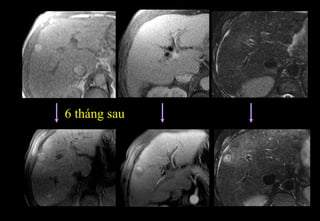

6 tháng sau

« Nốt trong nốt »

Nốt CHC giữa một nốt dị sản

• nốt tăngT2 trong một nốt giảmT2

• có thể tăng tín hiệu khi tiêm Gadolinium